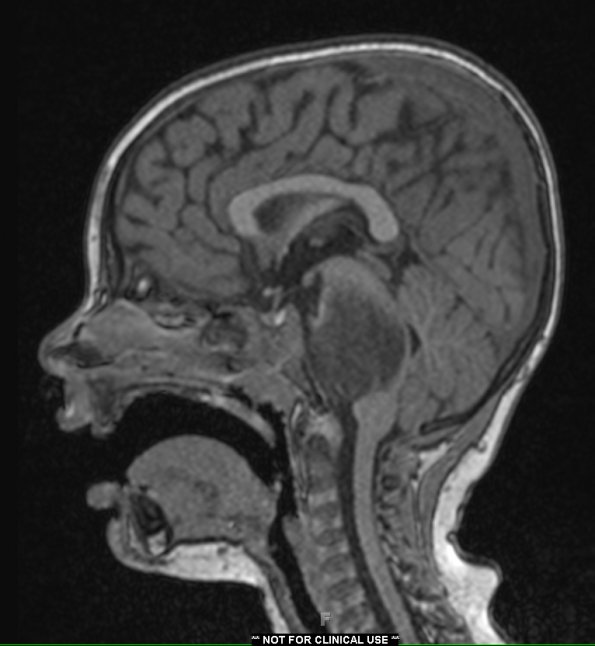

4A2 Diffuse midline glioma (DIPG) (Case 4) T1 W

4A2,3 The mass is hypointense in these T1-weighted scans with contrast.